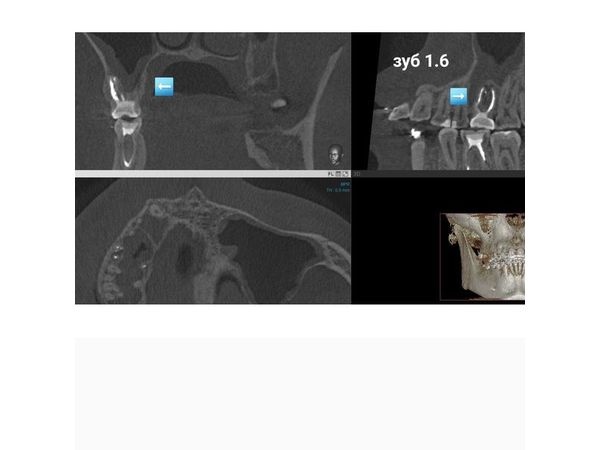

КЛКТ челюстно-лицевой области выявила очаг хронического воспаления в области верхушки мезиального (левого) корня зуба 1.6, второй мезио-букальный корневой канал (второй канал слева, ближе к щеке) был не запломбирован (пропущен).